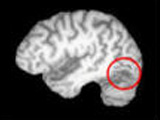

To gain new insight into the neural basis of object recognition, the research team used neuroimaging and behavioral investigations to study visual and object-selective responses in the cortex of healthy controls and a participant called SM who, following selective brain damage to the right hemisphere of the brain, exhibited object agnosia.

The researchers discovered that the functional organization of the "lower" visual cortex, where the image from the retina is initially processed, was similar in SM and control subjects. However, SM exhibited decreased object-selective responses in the brain tissue in and around the brain lesion, and in more distant cortical areas that are also known to be involved in object recognition. Unexpectedly, the decrease in object-selective responses was also observed in corresponding locations of SM's structurally intact left hemisphere.

"What was perhaps the most dramatic, controversial and counter-intuitive result was that while the lesion was in the right hemisphere, and quite small, we found that the same region in the left hemisphere was also not operating normally," Behrmann said.

Additionally, the researchers found that an area of the brain called the right lateral fusiform gyrus is vital for object recognition. There also appeared to be some functional reorganization in intact regions of SM's damaged right hemisphere, suggesting that neural plasticity is possible even when the brain is damaged in adulthood.